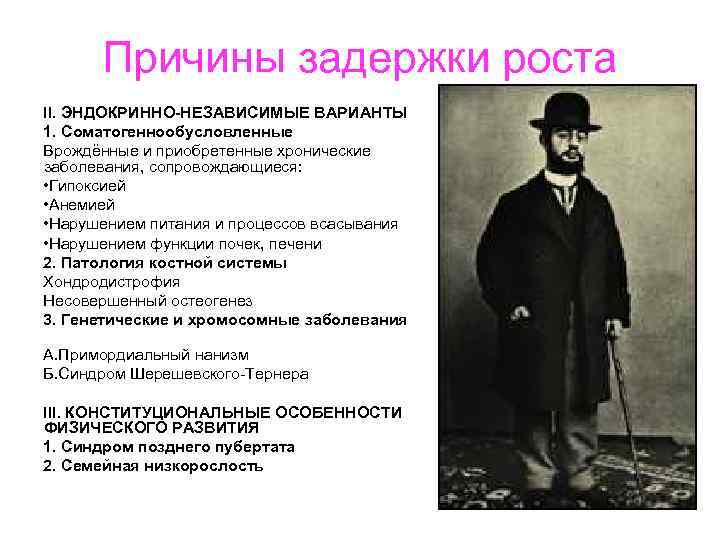

Причины задержки роста II. ЭНДОКРИННО-НЕЗАВИСИМЫЕ ВАРИАНТЫ 1. Соматогеннообусловленные Врождённые и приобретенные хронические заболевания, сопровождающиеся: • Гипоксией • Анемией • Нарушением питания и процессов всасывания • Нарушением функции почек, печени 2. Патология костной системы Хондродистрофия Несовершенный остеогенез 3. Генетические и хромосомные заболевания А. Примордиальный нанизм Б. Синдром Шерешевского Тернера III. КОНСТИТУЦИОНАЛЬНЫЕ ОСОБЕННОСТИ ФИЗИЧЕСКОГО РАЗВИТИЯ 1. Синдром позднего пубертата 2. Семейная низкорослость

Причины задержки роста II. ЭНДОКРИННО-НЕЗАВИСИМЫЕ ВАРИАНТЫ 1. Соматогеннообусловленные Врождённые и приобретенные хронические заболевания, сопровождающиеся: • Гипоксией • Анемией • Нарушением питания и процессов всасывания • Нарушением функции почек, печени 2. Патология костной системы Хондродистрофия Несовершенный остеогенез 3. Генетические и хромосомные заболевания А. Примордиальный нанизм Б. Синдром Шерешевского Тернера III. КОНСТИТУЦИОНАЛЬНЫЕ ОСОБЕННОСТИ ФИЗИЧЕСКОГО РАЗВИТИЯ 1. Синдром позднего пубертата 2. Семейная низкорослость